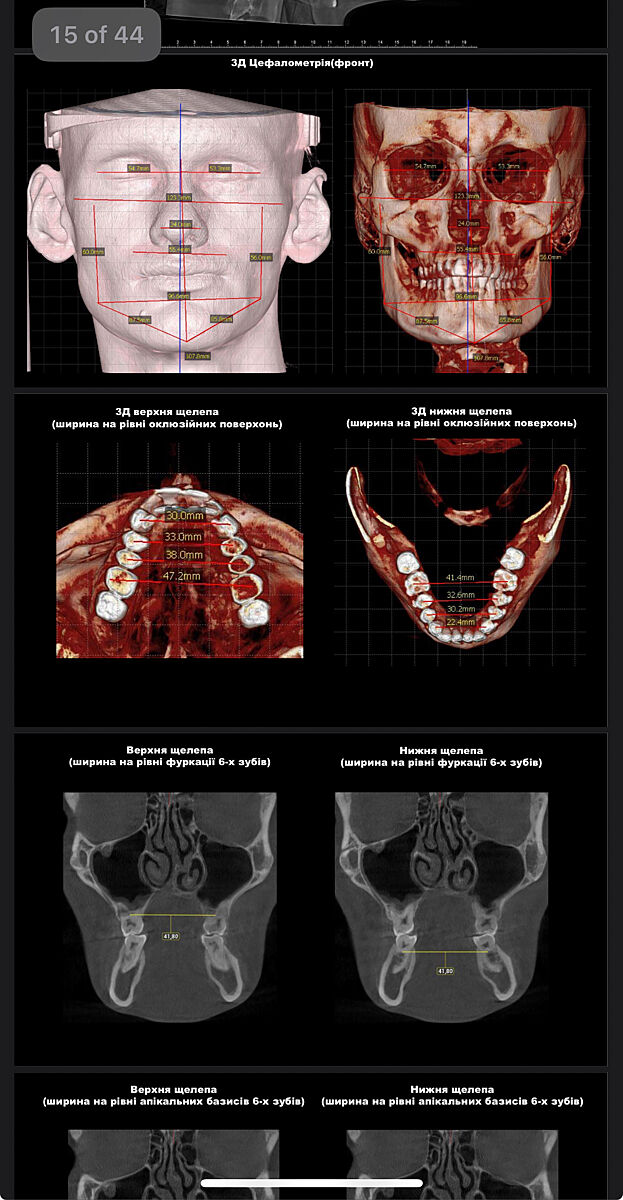

У сына не все так просто , поэтому по максимуму сделали тут . Заграницей уже врач ведет. Вот такое кт